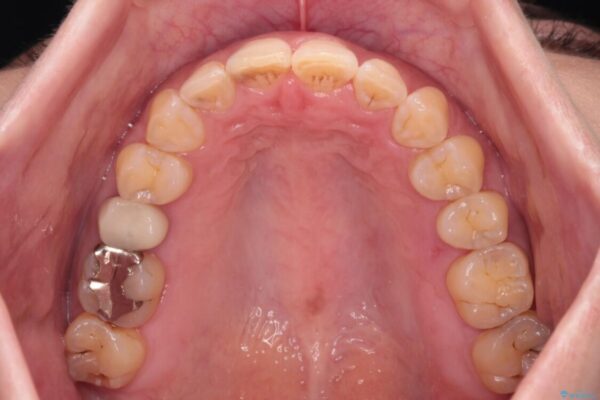

治療後について

舌の突出癖が原因で上下の歯に大きなスペースが生じていたため、舌のトレーニングをしっかり行っていただくことで、上顎歯列をスムーズに移動させることができました。

治療後

• 【モニター】飛び出た前歯を整えたい ワイヤー矯正治療 治療後画像